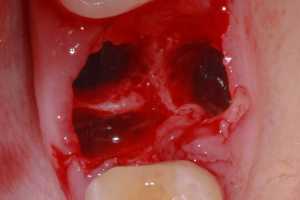

Удаление в молодом возрасте снижает риски постоперационной чувствительности и способствует быстрому заживлению. Молодые пациенты лучше переносят оперативное вмешательство, восстановительный период у них проходит более быстро и меньше влияет на повседневную деятельность. Так же у более молодых пациентов быстрее и полноценнее происходит заживление пародонта, в частности, в дистальной части второго моляра. Так же у таких пациентов отмечается более хорошее восстановление при повреждении нерва. Оперативное лечение предпочтительнее проводить в молодом возрасте, поскольку костная ткань менее плотная, а корни зубов до конца не сформировались. Идеальным моментом для удаления третьего моляра является тот временной промежуток, когда корни уже сформированы на 1/3, но еще не сформировались на 2/3 длины. Обычно это наблюдается в середине и конце подросткового периода, между 16 и 20 годами.